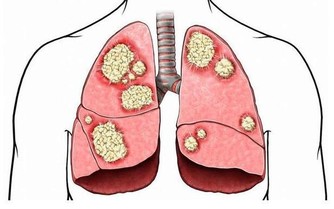

而甲醛的危害性,估計不用小編多說了。作為一級致癌物,長時間接觸甲醛,致癌風險也會增加。